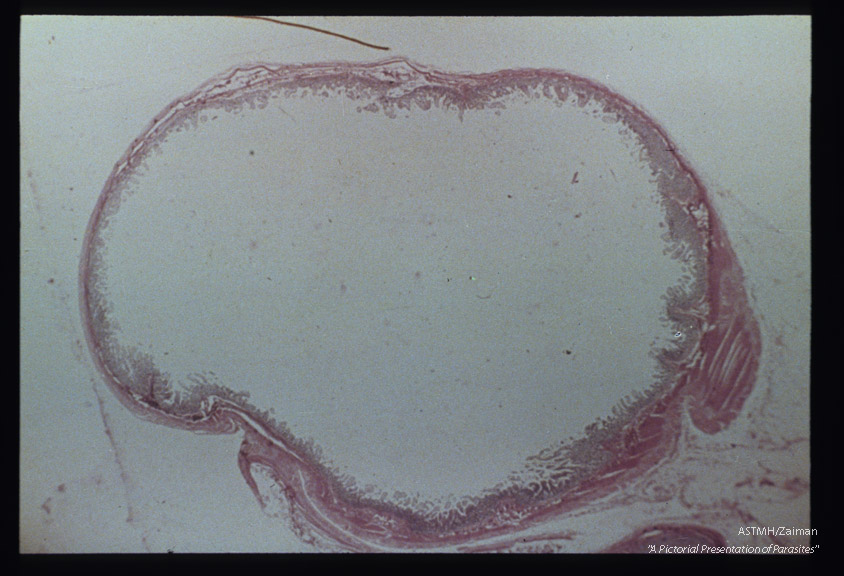

Gross pathology. Cross section of human gut showing atrophy of mucous layer.

Strongyloides stercoralis

Description: Gross pathology. Cross section of human gut showing atrophy of mucous layer.